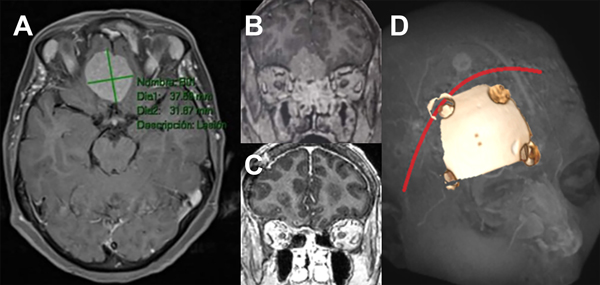

Figura 1: Imágenes representativas de paciente operado de meningioma de base de cráneo anterior de surco olfatorio. A: secuencia T1 con contraste de resonancia magnética, corte axial. B: Misma lesión corte coronal C: corte coronal de imagen posoperatoria. D: abordaje y craneotomía realizada.